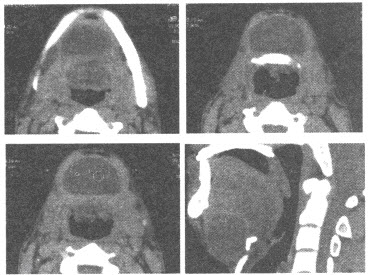

男,37岁,自觉颌下肿物7年。CT检查如图,应诊断为()

A:颌下皮样囊肿

B:颌下神经鞘瘤

C:颌下淋巴结结核

D:甲状舌管囊肿

E:以上均不是